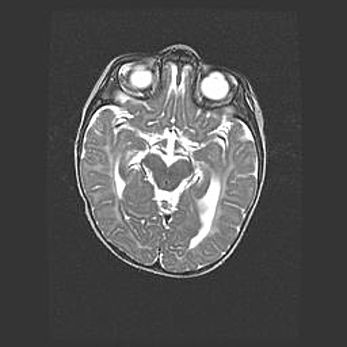

Наружная гидроцефалия с возможной атрофией височных областей.

Возраст: 28 дней

Вес: 3670 г

Пол: мужской

Окружность головы: 38 см

Срок гестации: 40 недель

Гидроцефалия головного мозга у новорожденных – это заболевание, которое характеризуется скоплением избыточного количества спинномозговой жидкости в желудочковой системе головного мозга в результате затруднения её перемещения от места выработки к месту поглощения в кровеносную систему или вследствие нарушения абсорбции. При открытой наружной форме гидроцефалии у новорожденных расширяются и переполняются субарахноидные пространства.

При нормотензивных  формах,  которые,  как  правило,  являются  следствием  перенесенных ишемических  повреждений  паренхимы  мозга,  возможно  сочетание микроцефалии  с нормотензивной гидроцефалией. В основе данных изменений лежит атрофия больших полушарий с преимущественной  локализацией  в  лобно-височных  областях.